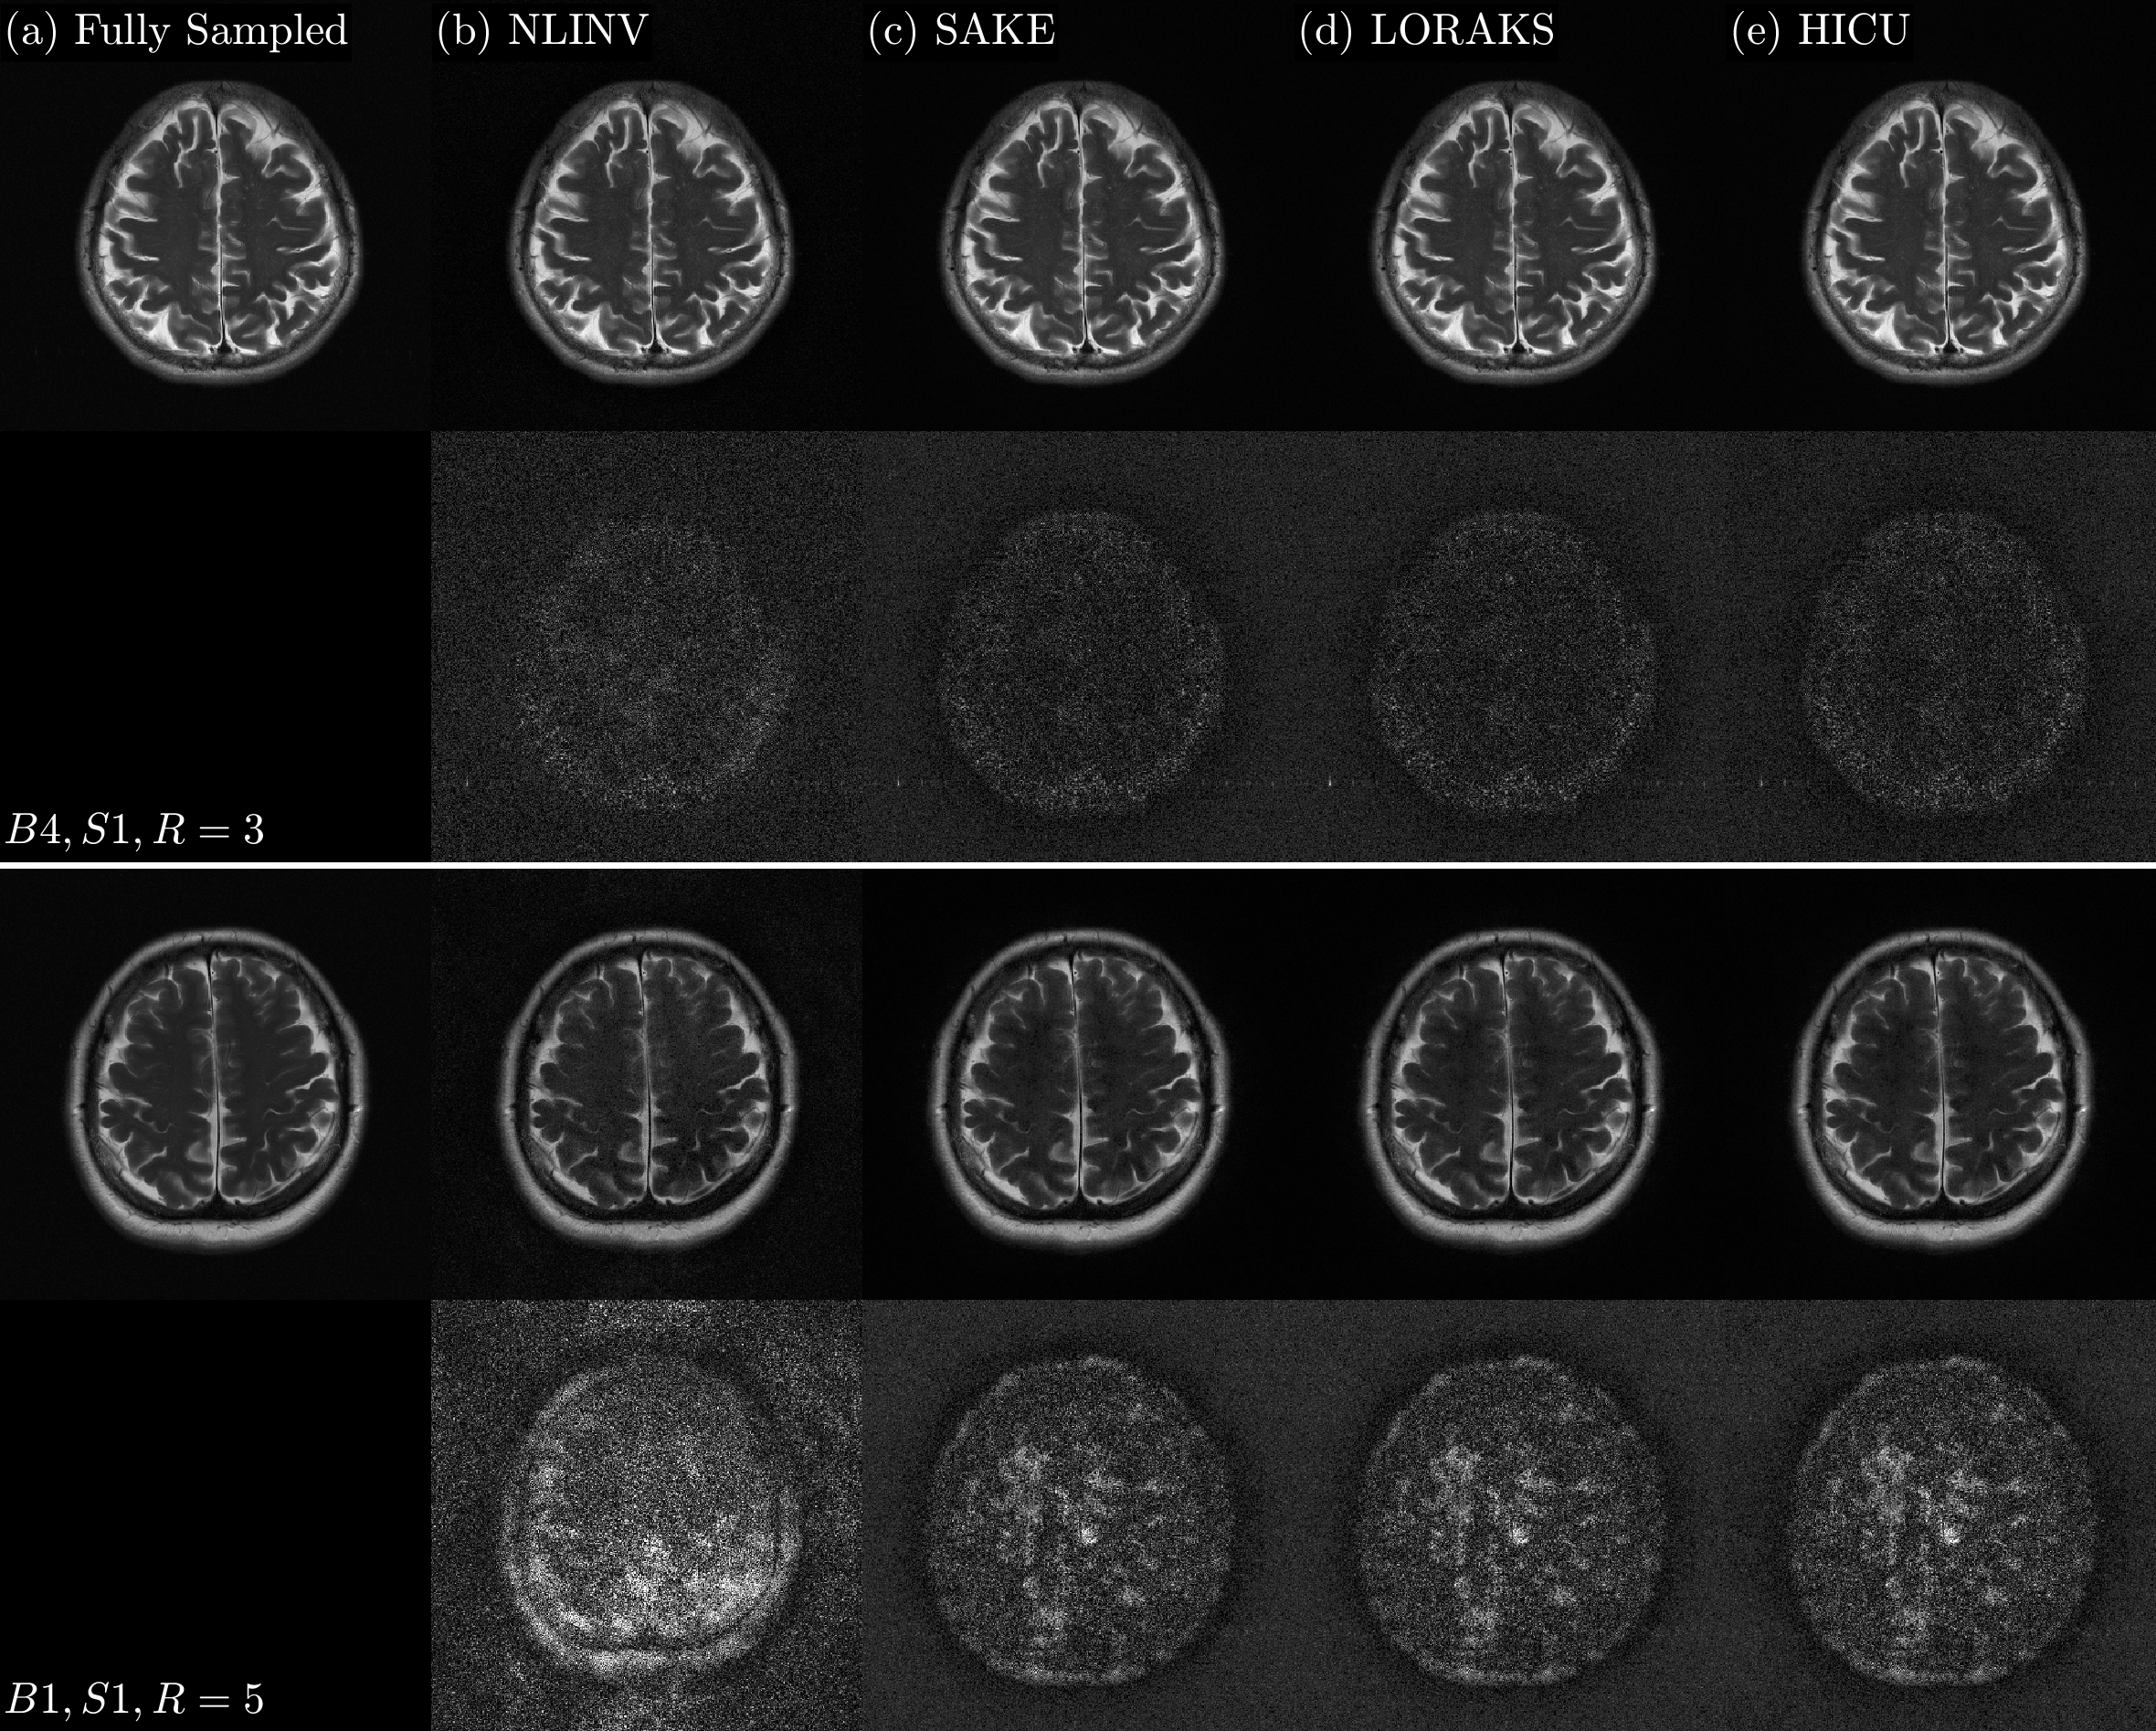

For Study I, the memory requirements for SAKE, LORAKS, NLINV, and HICU were approximately 450450450 MB, 450450450 MB, 130130130 MB, and 181818 MB, respectively. Figure 3 shows the average SER versus runtime for SAKE, LORAKS, and HICU for (S1,R=3𝑆1𝑅3S1,R=3) and (S1,R=5𝑆1𝑅5S1,R=5). Time in seconds is plotted logarithmically to illuminate computing time ratios and simultaneously view time on the scale of hours, minutes, and seconds. Figure 4 shows SER versus runtime for six choices of p𝑝p with CO disabled to explore the effect of the JL projection dimension, p𝑝p, for (B1,S1,R=3𝐵1𝑆1𝑅3B1,S1,R=3); this figure also shows SER versus runtime for four HICU variants with and without the CO and JL numerical strategies for (B1,S1,R=5𝐵1𝑆1𝑅5B1,S1,R=5). Figure 5 shows the SSoS reconstruction images for (B4,S1,R=3𝐵4𝑆1𝑅3B4,S1,R=3) and (B1,S1,R=5𝐵1𝑆1𝑅5B1,S1,R=5), the two datasets that yielded the highest and lowest SER from Figure 2.

HICU provides a fast and memory-efficient computational procedure for structured low-rank matrix completion. Using 2D brain images, Study I suggests, from Table 1 and Figure 3, that HICU can provide over an order of magnitude speedup compared to SAKE and LORAKS while providing comparable image quality across all metrics and significantly reduced memory requirement. Likewise, Figure 5 shows qualitatively very similar converged reconstruction results for SAKE, LORAKS, and HICU; the similarity is expected in that all three methods exploit the rank deficiency of the Hankel data matrix. The annihilating kernel support used in Study I was rectangular to conform with SAKE implementation (33); however, LORAKS and HICU can support circumscribing circular or spherical kernel masks that have been observed to yield SER gains (11). NLINV produced much lower image quality in this application than the other methods and required 1.51.51.5 to 444 times more computation time than HICU.

Figure 5: Top row: SSoS images for SAKE, LORAKS, HICU at one hour, and NLINV at the final iteration. Bottom row: 10×10\,\times absolute error relative to fully sampled k-space.